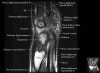

- Coronal section

Coronal T1 imaging evaluates bone marrow signal (ex. increased in avascular necrosis) and the relationship of the osseous structures to each other (ex. scapholunate disassociation).